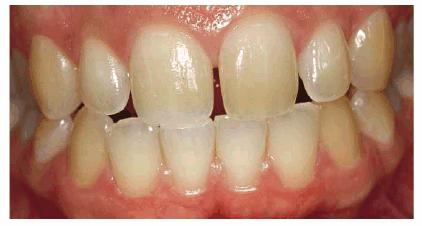

Figure 16-2A and B: Total neglect resulted in severe staining

of this patient's teeth.